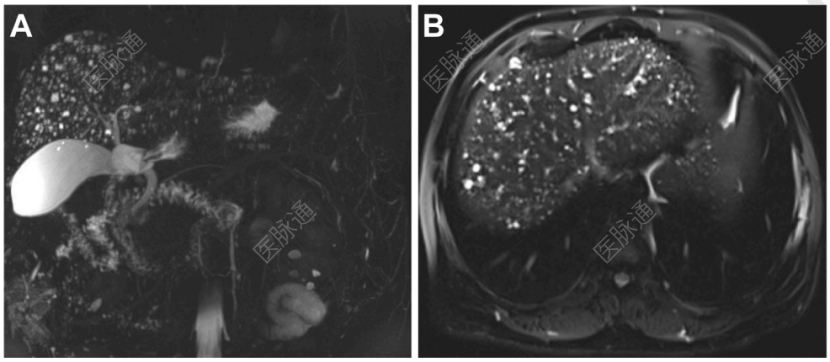

磁共振胰胆管成像(MRCP)及磁共振成像

(MRI)检查,结果可见沿胆管走行的弥漫性、圆形、T2高信号病灶,部分与胆管树相连(图A、B)。